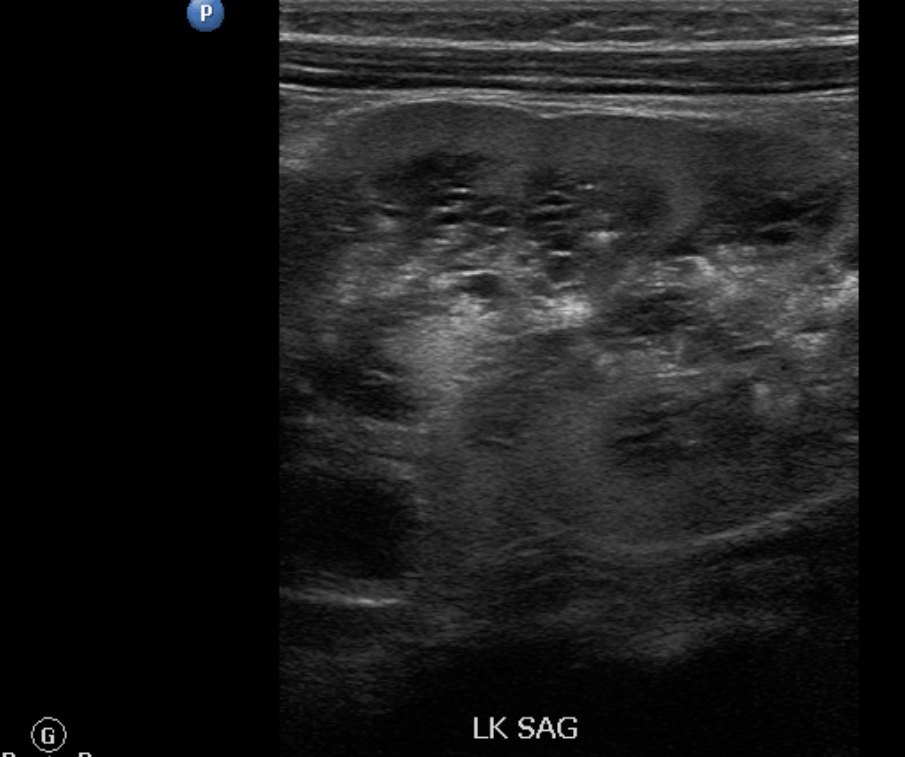

19F Hypertensive

kypokalaemia

elevated aldosterone

Juxtaglomerular Tumor (Reninoma)

Reninoma is a tumour of the cells of the juxtaglomerular apparatus that produces excessive amounts of renin, resulting in a secondary form of hyperaldosteronism, manifesting clinically with hypertension (HT) and hypokalaemia1. This renal tumour is predominant in females, with a peak incidence between the second and third decade of life and, although uncommon, it is a treatable cause of HT2. It should be suspected in any patient with refractory HT associated with hypokalaemia and high levels of aldosterone.

We present the first case of reninoma reported in Argentina in a young woman with refractory HT and hypokalaemia.

In 1967, Robertson et al.6 reported the first renin-producing tumour. Kihara et al. later called them “juxtaglomerular cell tumours”7. These tumours are very uncommon, with their incidence peaking between the second and third decade of life and they are predominantly found in females, originating in the myoendocrine cells of the renal juxtaglomerular apparatus, although the production of renin by different tumours has also been demonstrated, such as Wilms tumours, carcinoid tumours, renal oncocytoma and renal cell carcinoma8,9. In accordance with the presence or absence of symptoms, JCT may occur as: a “typical” variant in the majority of cases and manifests with HT, hypokalaemia, high plasma renin and secondary hyperaldosteronism; an “atypical” variant, in which HT is not accompanied by hypokalaemia; and a third “non-functioning” variant, which occurs without HT and with normal levels of potassium10,11.

Plasma renin activity (PRA) and plasma aldosterone (PA)